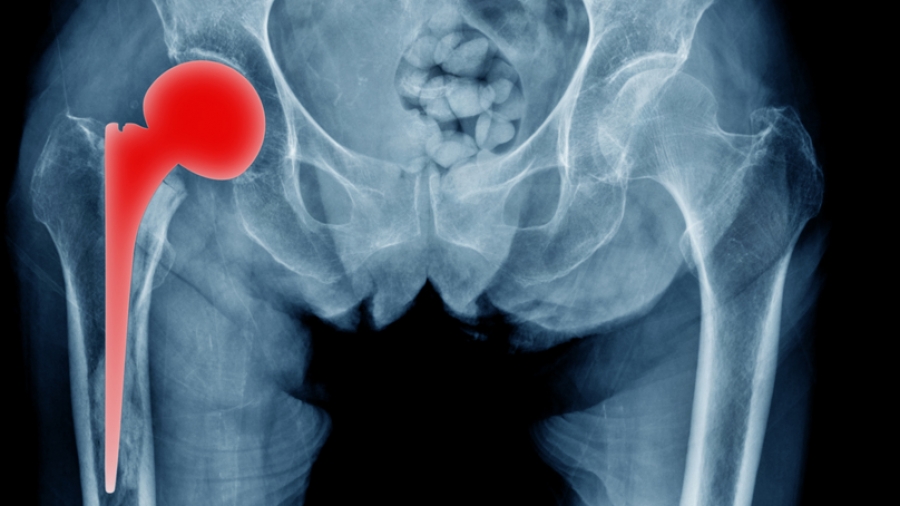

Η ολική αρθροπλαστική ισχίου είναι μια επέμβαση που κατά κύριο λόγο εφαρμόζεται ως τελική θεραπευτική λύση για την αντιμετώπιση της οστεοαρθρίτιδας του ισχίου. Η οστεοαρθρίτιδα γενικά αποτελεί μια εκφυλιστική νόσο των αρθρώσεων που επιφέρει πόνο και περιορισμό της κινητικότητάς τους. Αυτά τα συμπτώματα μπορεί να είναι τόσο έντονα που να οδηγήσουν ακόμα και σε αδυναμία εκπλήρωσης καθημερινών δραστηριοτήτων ρουτίνας.

Η ολική αρθροπλαστική του ισχίου βελτίωσε και συνεχίζει να βελτιώνει την ποιότητα ζωής εκατομμυρίων ασθενών εδώ και δεκαετίες. Ωστόσο, για μεγάλο χρονικό διάστημα παρέμενε μια βαριά, συχνά αιμορραγική επέμβαση που απαιτούσε μακρά νοσηλεία και αποκατάσταση. Στην πορεία των ετών η ορθοπαιδική χειρουργική εξελίχθηκε επιστημονικά και ταυτόχρονα εξελίχθηκε και η επιστήμη των υλικών που χρησιμοποιούνται στα χειρουργεία. Αποτέλεσμα αυτών των εξελίξεων αποτελούν οι νέες χειρουργικές τεχνικές που εντάσσονται στο χειρουργικό οπλοστάσιο του ορθοπαιδικού χειρουργού για την αντιμετώπιση της οστεοαρθρίτιδας του ισχίου.

«Την τελευταία πενταετία στο Metropolitan Hospital υιοθετήθηκε στην καθημερινή χειρουργική πράξη η τεχνική SuperPATH, μια σύγχρονη, εξελιγμένη τεχνική ολικής αρθροπλαστικής ισχίου με προσπέλαση ελάχιστης επεμβατικότητας, η οποία συνοδεύεται από επιστημονικά δεδομένα τεκμηρίωσης στη διεθνή βιβλιογραφία.

Στόχος της συγκεκριμένης χειρουργικής τεχνικής ελάχιστης επεμβατικότητας είναι η  αντικατάσταση της άρθρωσης υπό συνθήκες μέγιστης προστασίας των μαλακών μορίων της περιοχής της άρθρωσης του ισχίου. Αυτό σημαίνει ότι πρώτιστο ζητούμενο αυτής της επέμβασης είναι το λειτουργικό αποτέλεσμα, ενώ το αισθητικό αποτέλεσμα που, μερικές φορές, προτάσσει ο ασθενής, παρανοώντας το συνολικό νόημα της επέμβασης, εξαρτάται από το μέγεθος της τομής που γίνεται για την προσπέλαση της περιοχής.

Συνεπώς, γίνεται μεν η προσπάθεια η τομή να είναι η ελάχιστη δυνατή, καθώς αυτή είναι η άμεση εικόνα που έχει ο ασθενής από το χειρουργείο, ωστόσο δεν γίνεται αντικατάσταση άρθρωσης με εισαγωγή υλικών χωρίς την ύπαρξη επαρκούς τομής. Η τομή είναι τόση ώστε να επιτευχθεί η μέγιστη προστασία των μαλακών μορίων και των τενόντων της περιοχής που αποτελεί την προϋπόθεση για την πρώιμη κινητοποίηση του ασθενούς, το μεγαλύτερο εύρος κίνησης της άρθρωσης και την ελαχιστοποίηση του μετεγχειρητικού πόνου», εξηγεί ο ιατρός.